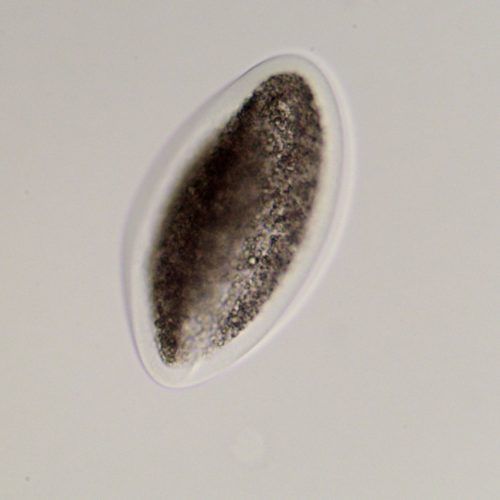

- Selective transport: Fertilization occurs and the embryo is formed within the oviduct. It remains in the oviduct for the first five and a half days after fertilization, until it signals the oviduct to move it into the uterus with the production of a specific form of prostaglandin. Without this signal, the oviduct tends to retain ova that are not fertilized or embryos that do not reach this stage of development. This means, unlike most domestic animals, unfertilized equine oocytes will generally not be recovered on a uterine flush unless they have accompanied an embryo into the uterus.